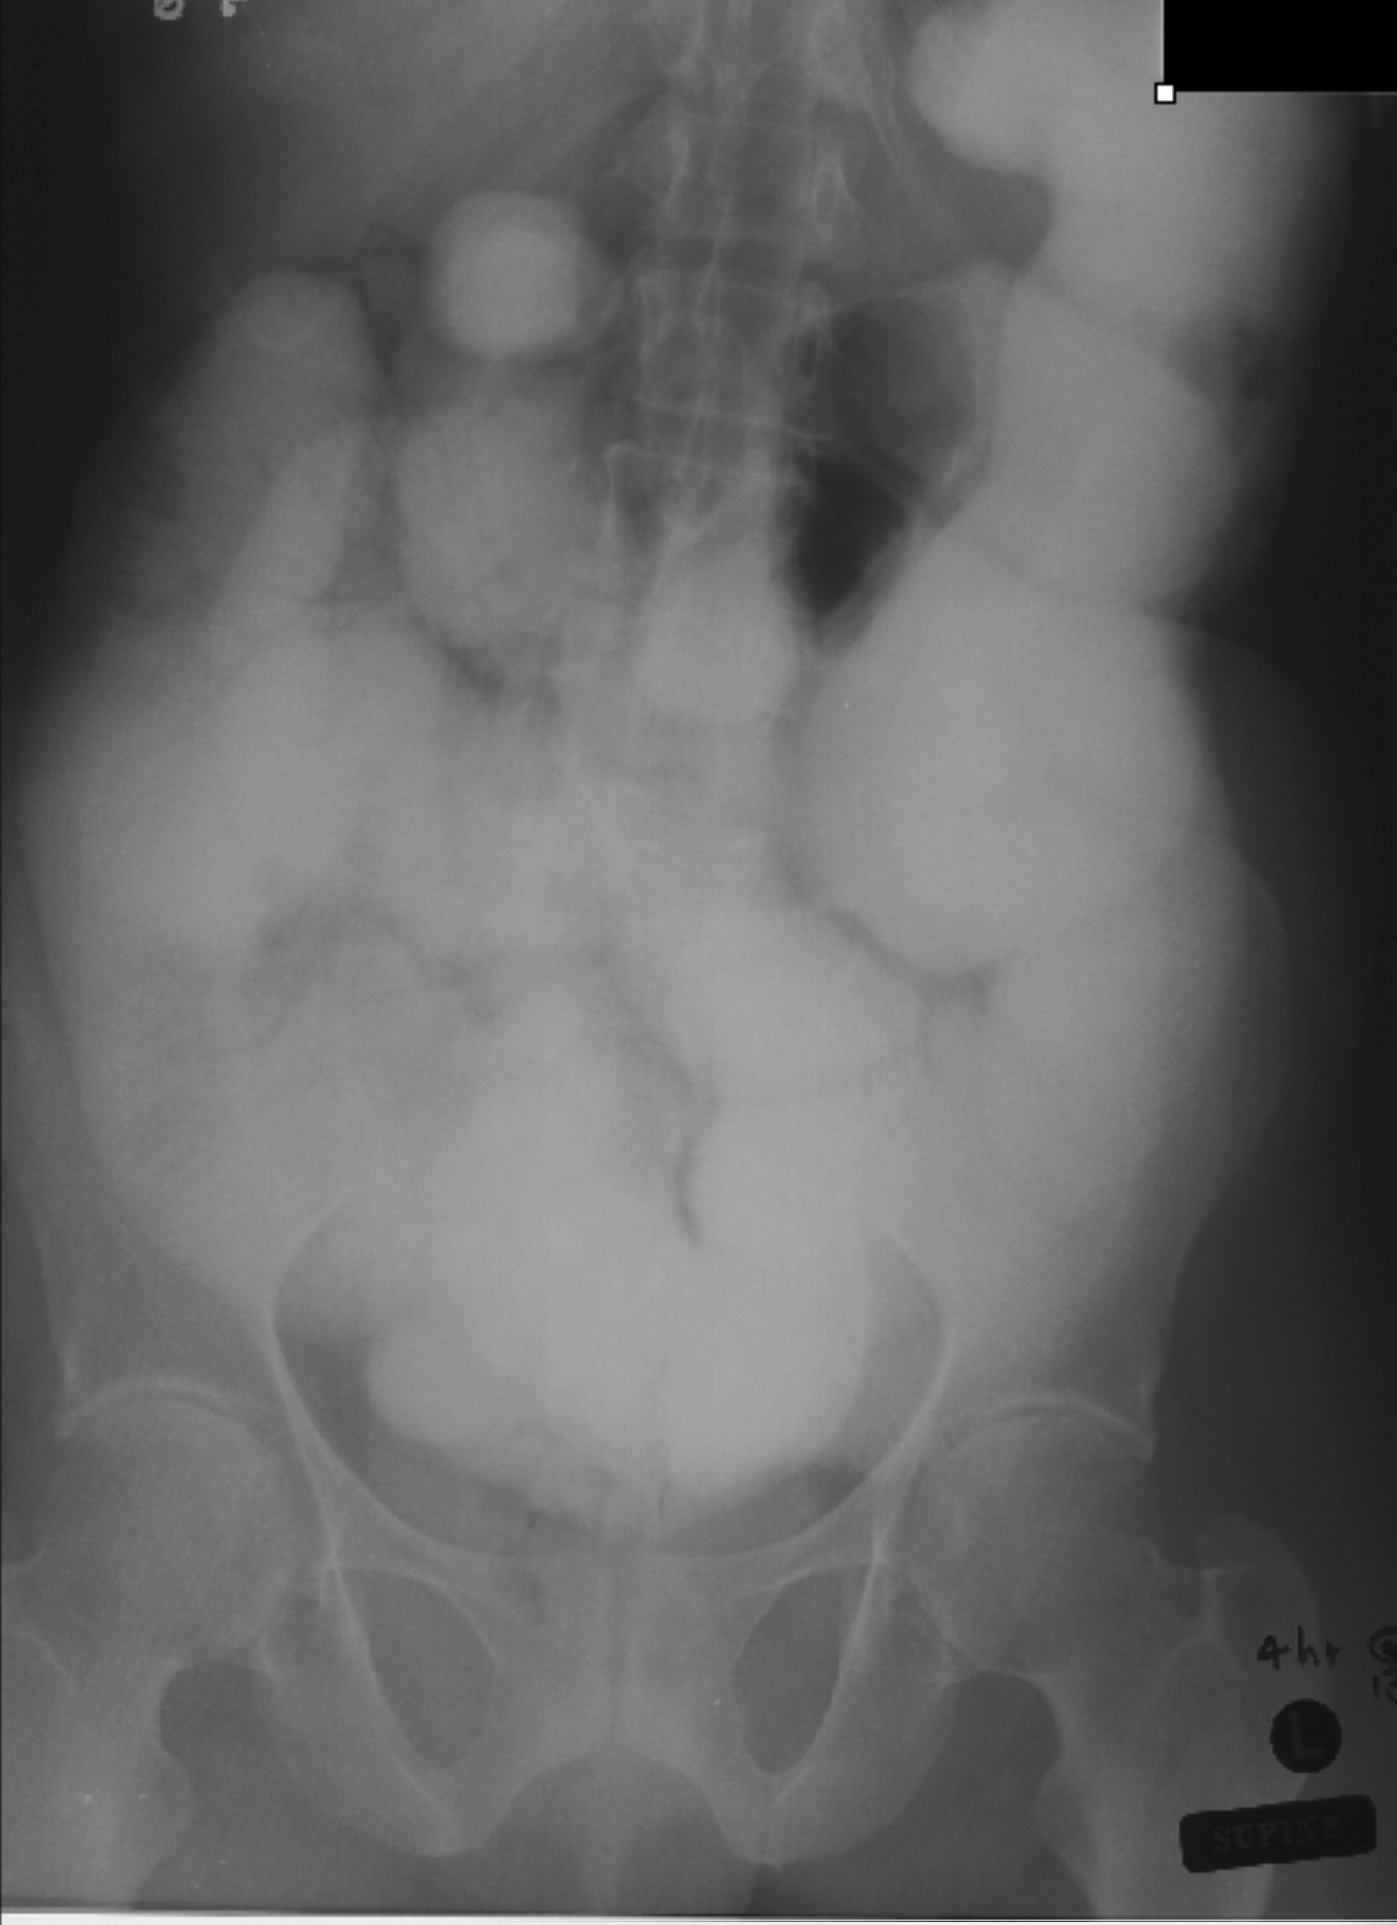

Small bowel obstruction is a common clinical presentation that presents a diagnostic conundrum. Over the last 2 decades, there has been a paradigm shift in the radiological investigation of small bowel obstruction (SBO) and in the indication for and timing of surgical intervention. Cross sectional imaging (predominantly computed tomography) has largely replaced the widespread use of radiographic small bowel follow-through studies as the imaging modality of choice for SBO. This article illustrates the current imaging modalities available for diagnosis of small bowel obstruction. (Full text available online at www.medpharm.tandfonline.com/ojfp) S Afr Fam Pract 2015; DOI: /10.1080/20786190.2014.977052